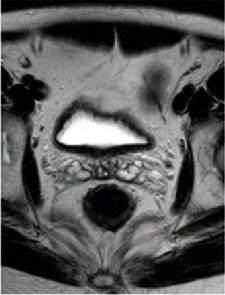

Pre- and post-treatment MRI was performed with a 1.5-tesla system (Intera R10, Philips Healthcare) using an eight-element pelvic phased-array surface coil. The subjects were imaged in the prone position after the placement of a thin rectal catheter in the rectum.

After initial localization imaging, researchers acquired MR images of the pelvis and rectum, with T2-weighted images obtained in the transverse, coronal, and sagittal planes during the scanning time of approximately 30 minutes.

The MR images calculated the mean tumor volume was 58 cm3 ± 75 before chemotherapy/radiation treatment and 20 cm3 ± 31 after therapy. The mean tumor volume reduction ratio in all patients was 68% ± 23.